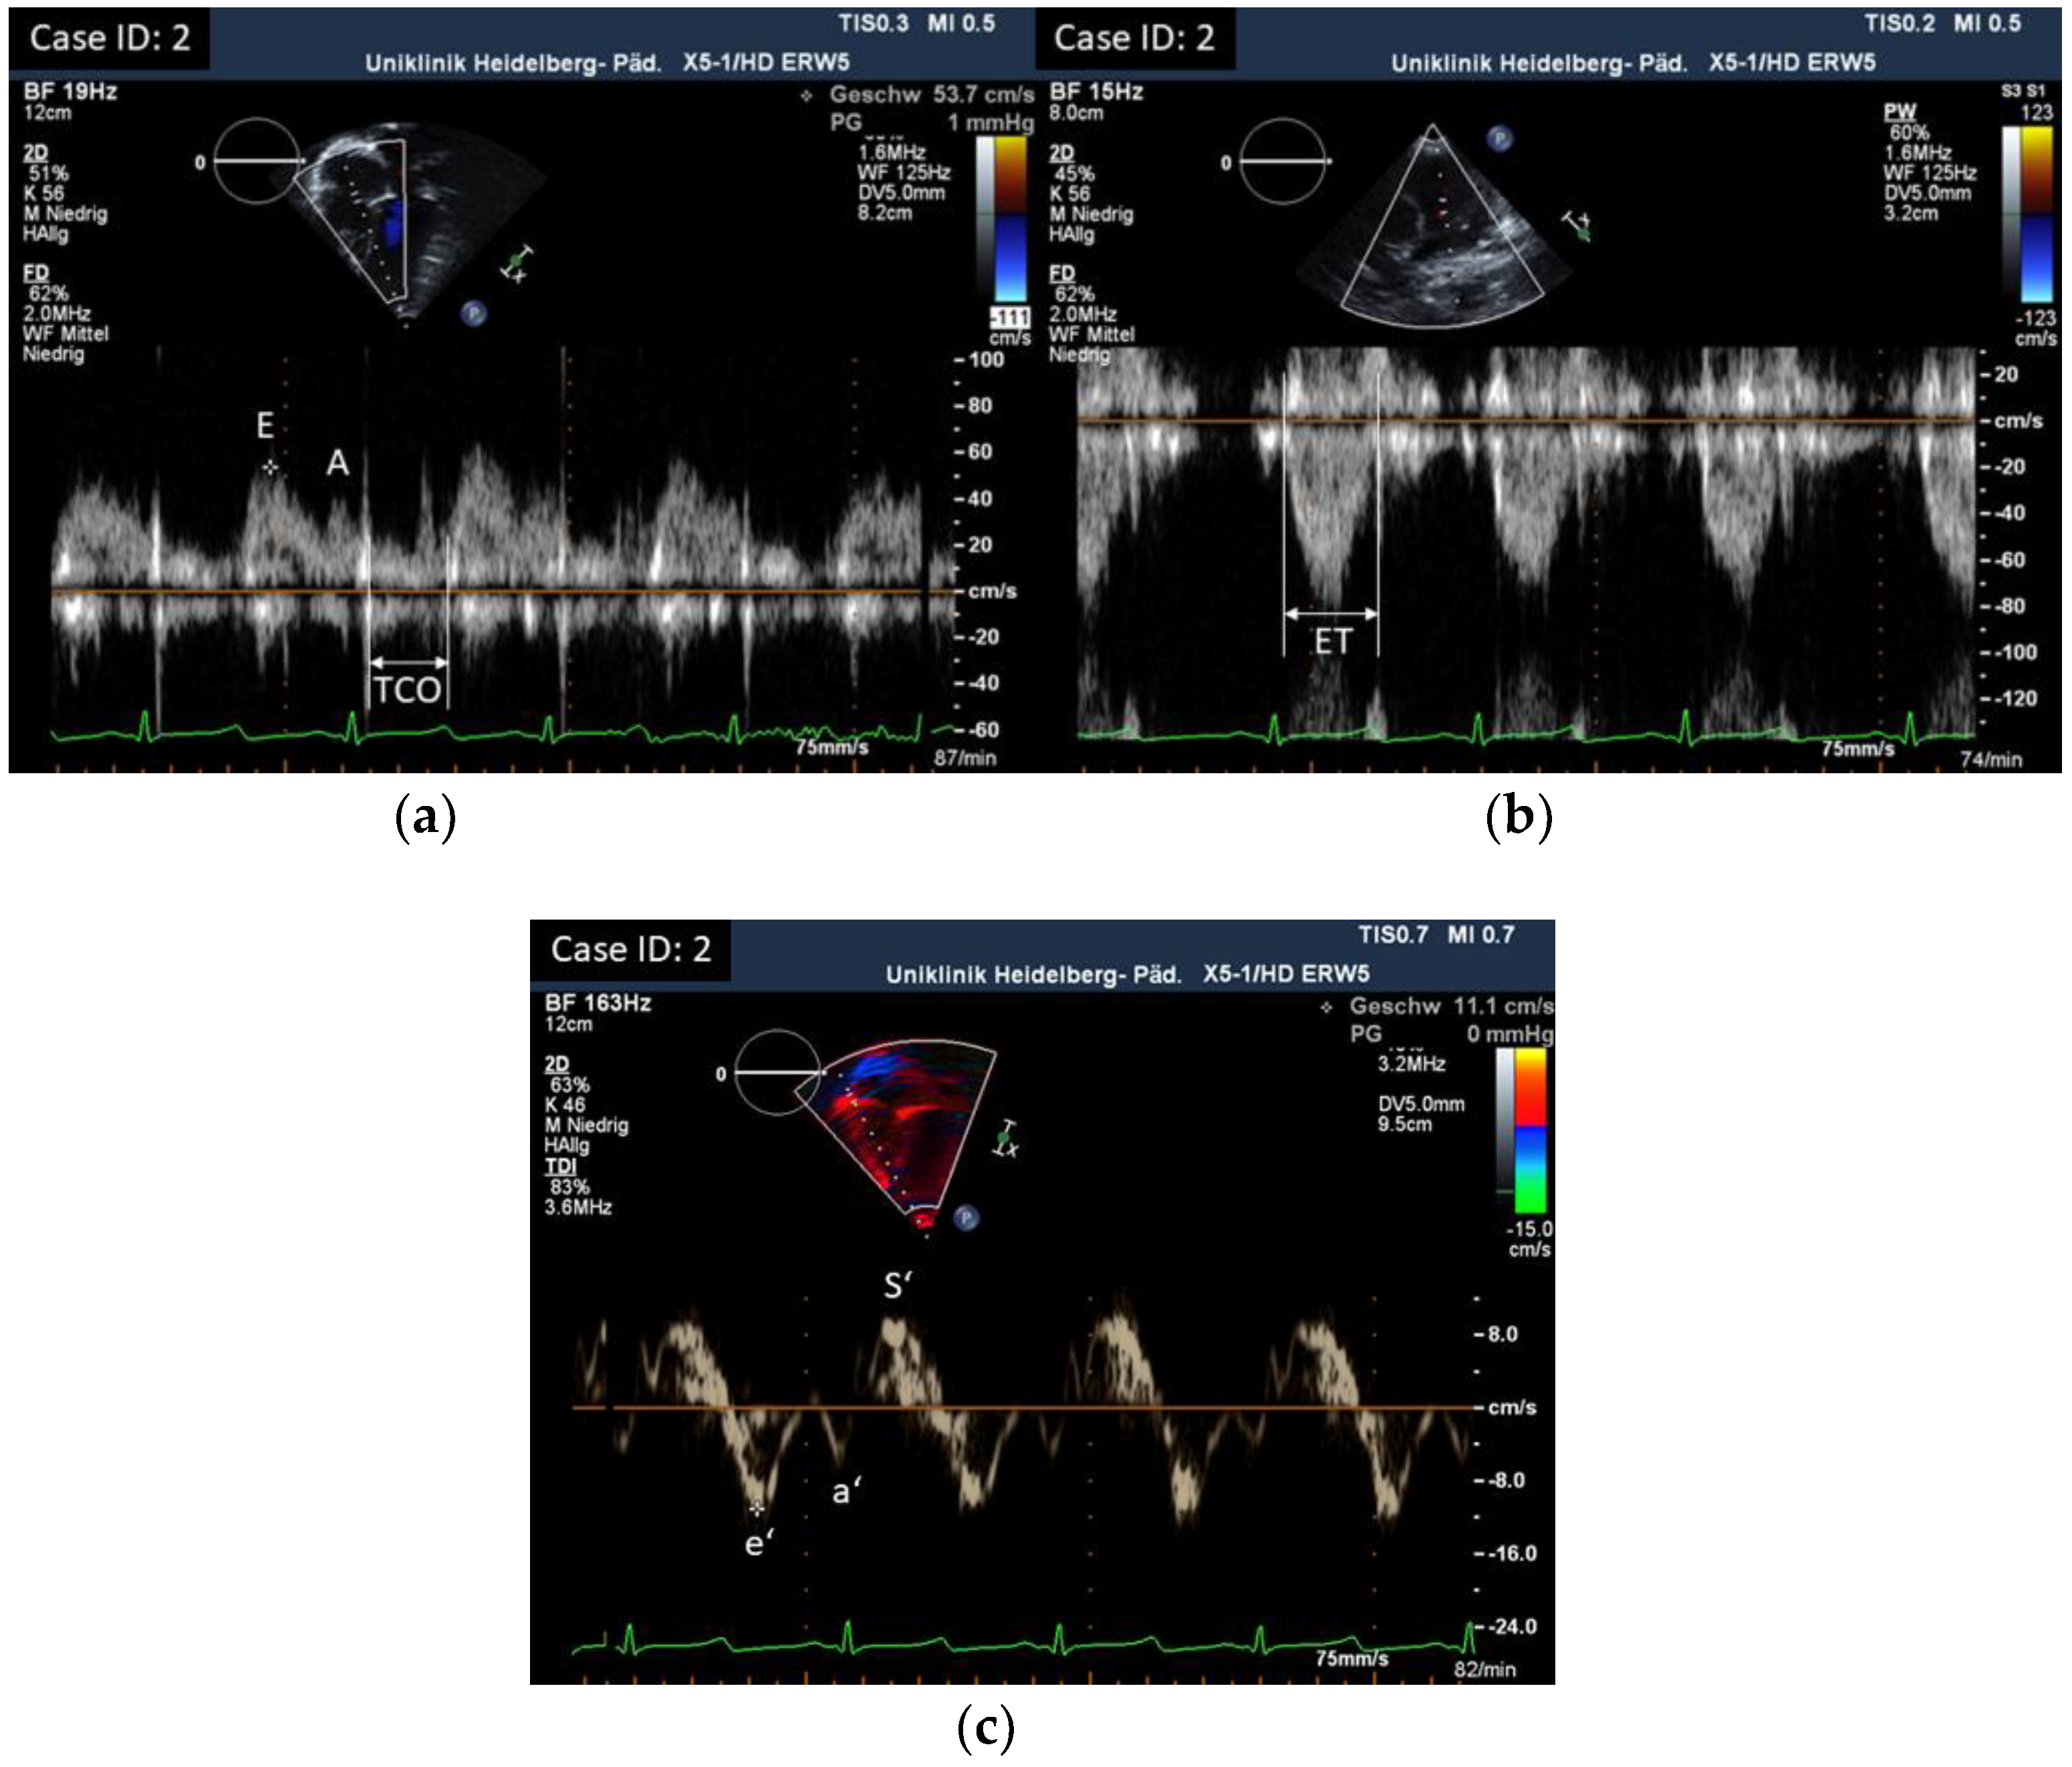

3.2. Results of Echocardiographic Measurements